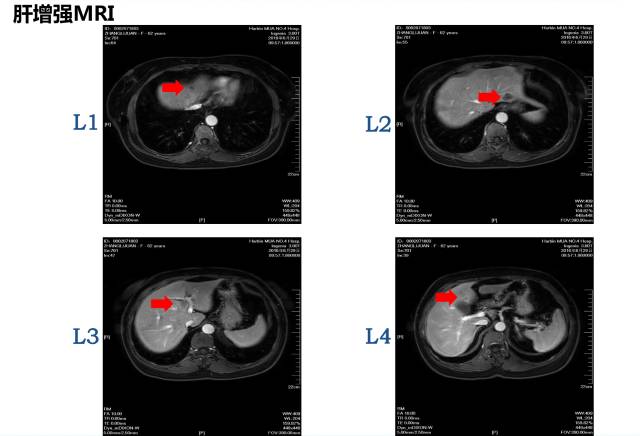

病理:盲肠腺癌肝脏MRI:共8枚病灶

1 2 肝转移病灶

3 右半结肠肿瘤